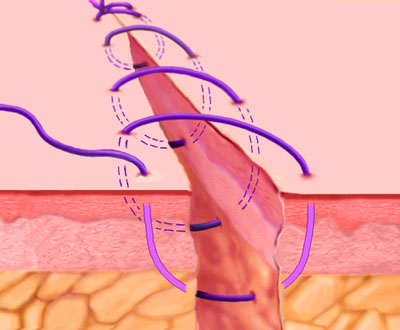

این نوع بخیه تحت نام بخیه ممتد یا همان continuous هم در بخش بالینی ما شناخته شده است شکل کاملا واضح است اما اگر باز هم مشکلی بود پیغام بگذارید تا توضیح کامل فارسی بگذارم.

Running, or Continuous Stitch

The "Running" stitch is made with one continuous length of suture material. Used to close tissue layers which require close approximation, such as the peritoneum. May also be used in skin or blood vessels. The advantages of the running stitch are speed of execution, and accommodation of edema during the wound healing process. However, there is a greater potential for malapproximation of wound edges with the running stitch than with the interrupted stitch